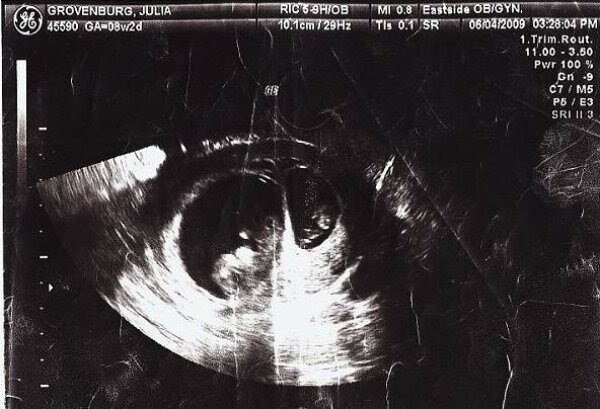

В положенный срок #семейная пара пришла на ультразвуковое исследование. То что врачи увидели на #УЗИ их озадачило. Это были дети на разных стадиях развития, не #близнецы.

Ультразвук на котором видно два плода на разных стадиях развития dailymail.co.uk ( Источник заимствования - ресурсы мировой сети)

Этот #феномен называется #суперфетация - оплодотворение второй яйцеклетки через некоторое время после начала беременности. В результате, в матке женщины, развиваются два #плода, возраст которых различен. И эти дети не близнецы. Такая история встречалась всего у 11 женщин на земле.